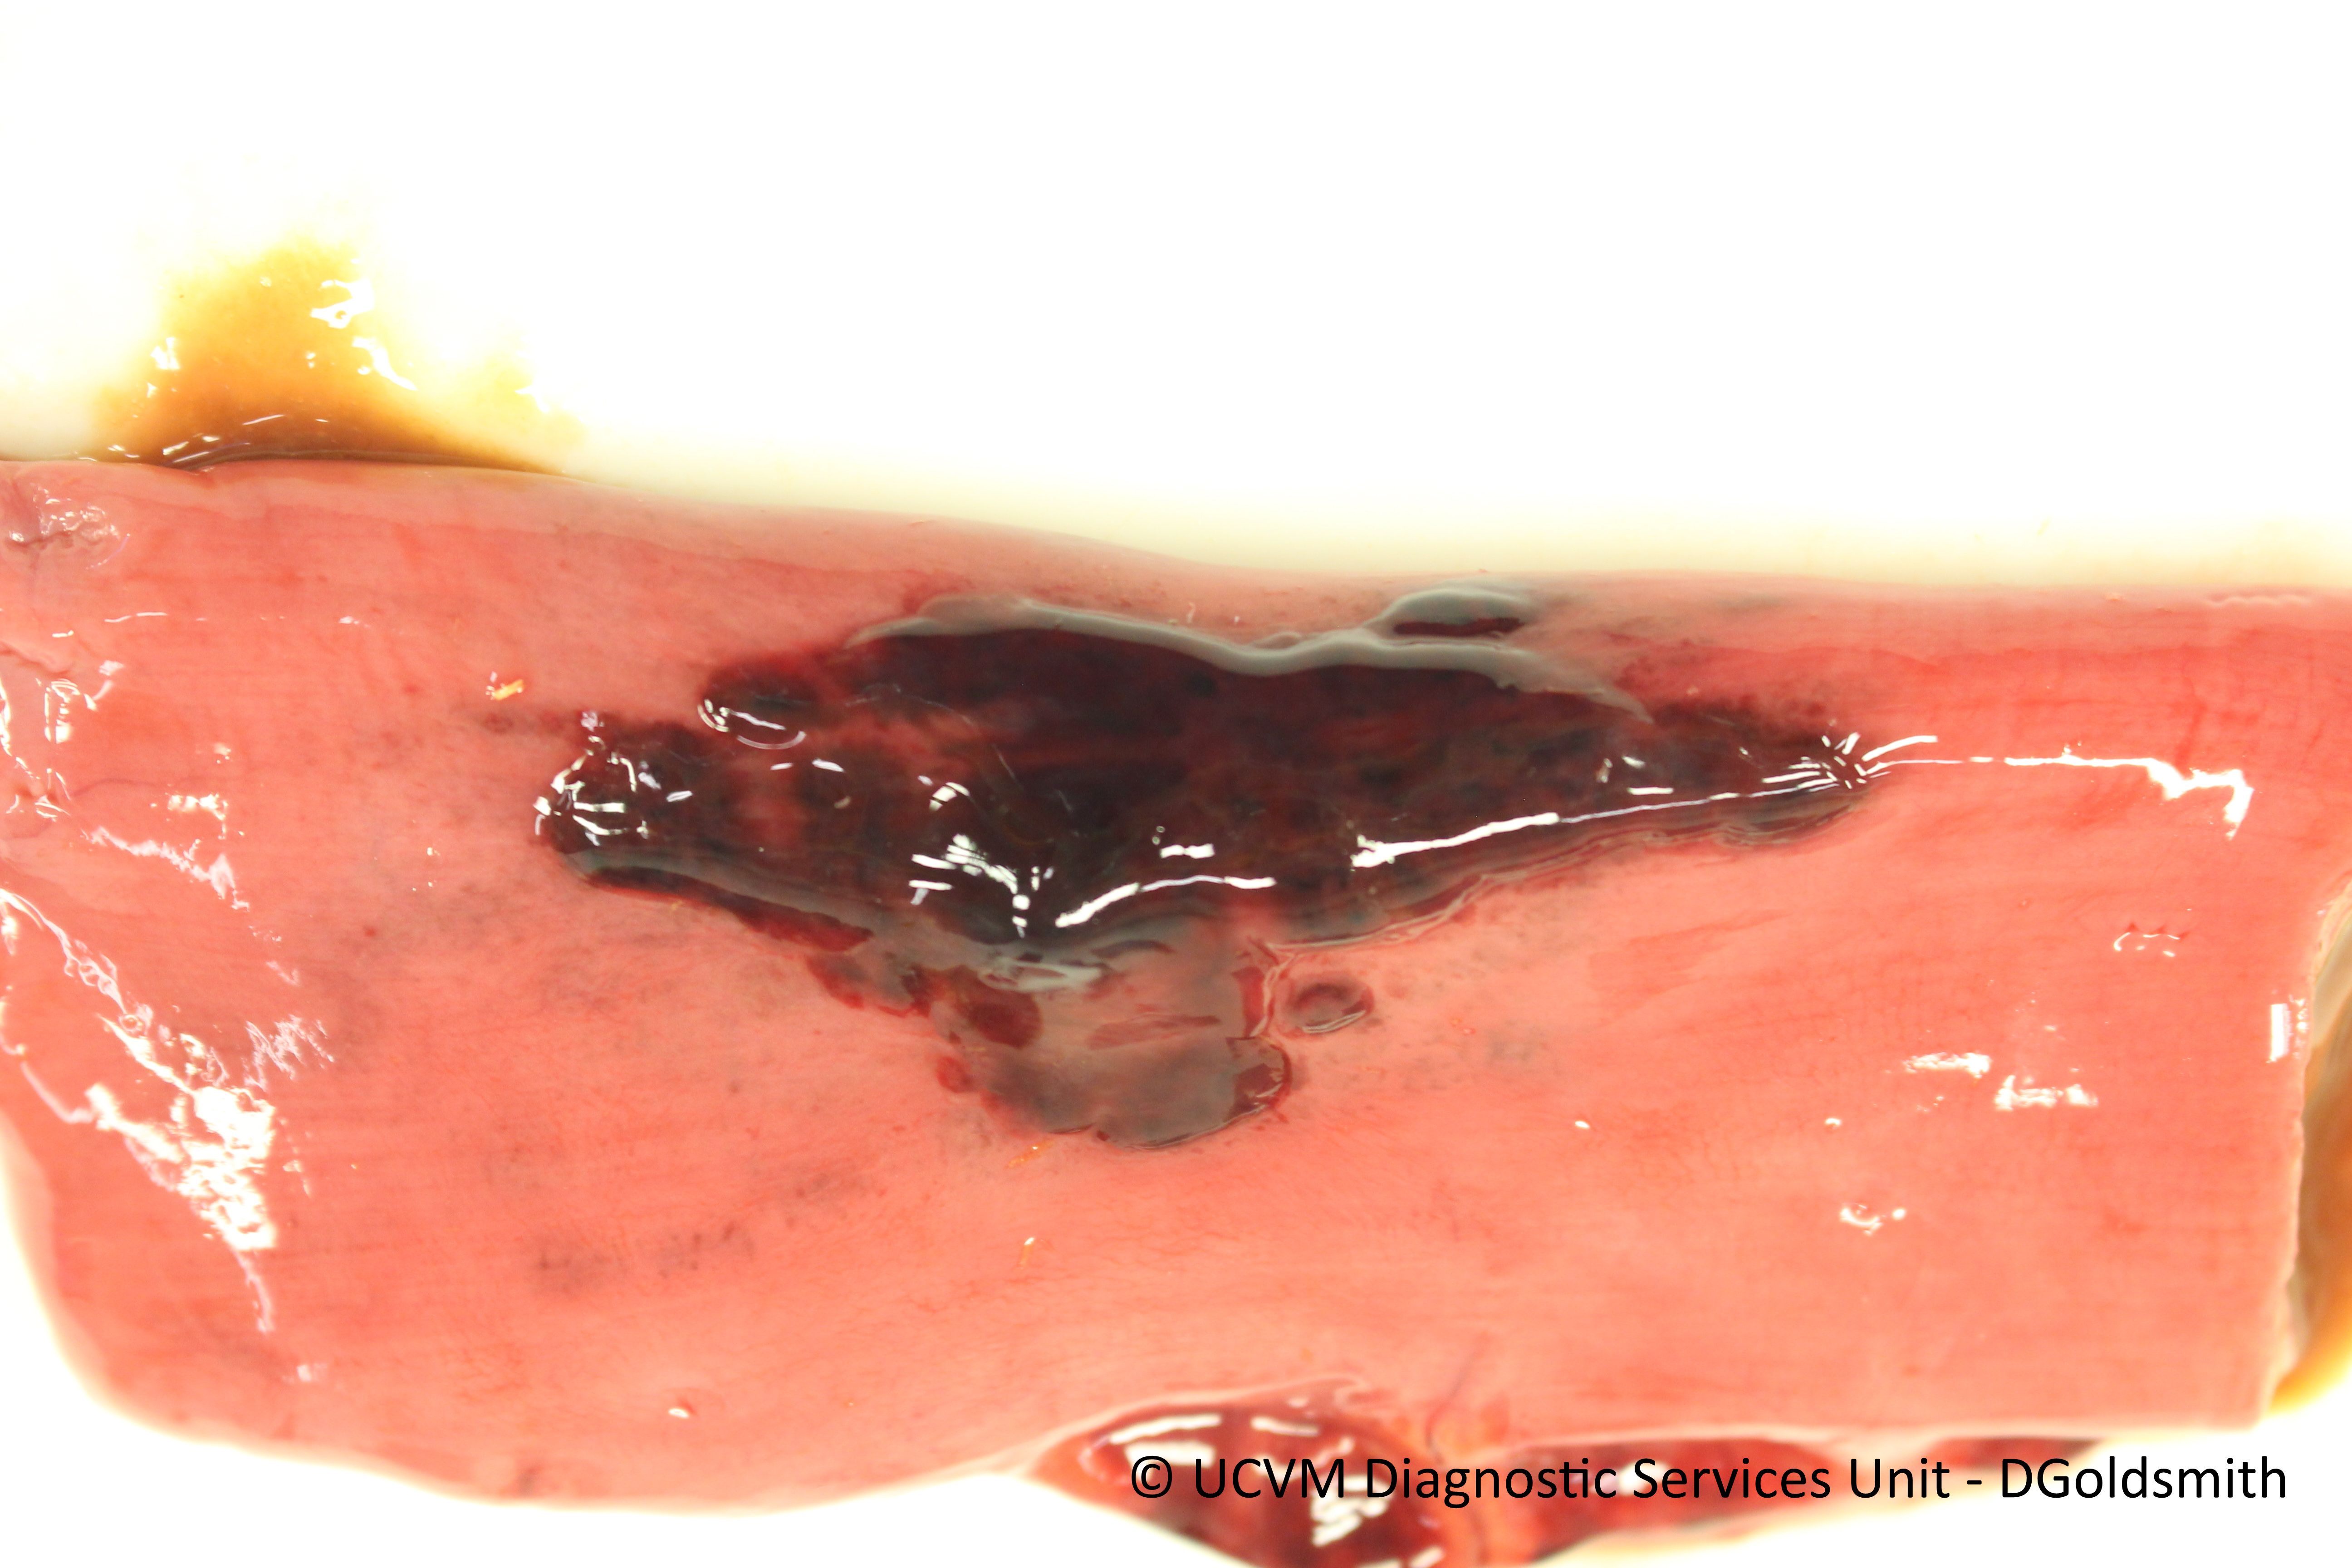

Small intestine, not ileum, with hemomelasma ilei like lesions with focal necrosis

Focal mural inflammation with eosinophilic granulomas suspect secondary to migrating parasites